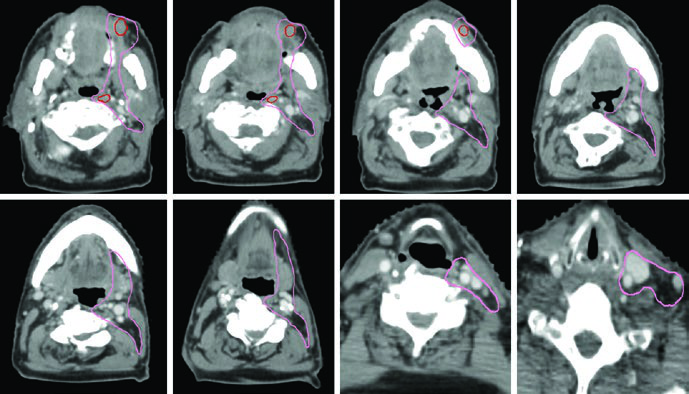

A irradiação nodal eletiva deve ser considerada caso a caso. Linfonodos eletivos fazem sentido para ENB e carcinoma espinocelular avançado, especialmente quando a origem é o seio maxilar ou quando há envolvimento de áreas com suprimento linfático extenso — nasofaringe, mucosa, pele, bochecha, nariz anterior, gengiva maxilar ou crista alveolar.

A drenagem nodal regional segue padrões previsíveis: linfonodos retrofaríngeos e níveis IB–IV. O nível V deve ser incluído quando há envolvimento da nasofaringe. Cobertura de linfonodos faciais deve ser considerada para tumores da cavidade nasal. A maioria dos tumores primários são estruturas de linha média, justificando irradiação nodal bilateral. A exceção são cânceres do seio maxilar, que recebem irradiação nodal unilateral.

O GTV deve ser delineado usando todas as informações clínicas relevantes de endoscopia, TC, RM e PET. O CTV de alto risco deve cobrir todos os sítios iniciais de doença e regiões potenciais de disseminação subclínica. Todas as imagens pré-operatórias devem ser avaliadas para garantir que o volume tumoral inicial esteja coberto.

A RM deve ser usada em todos os casos para auxiliar o delineamento, exceto quando contraindicada. Carcinomas adenoides císticos são altamente neurotrópicos, portanto os volumes devem cobrir nervos aferentes e eferentes locais até a base do crânio. ENB surge na cavidade nasal superior e tende a invadir a lâmina cribriforme e fossa craniana anterior precocemente.

A tabela abaixo detalha as considerações anatômicas específicas por subsítio para delineamento do CTV primário.